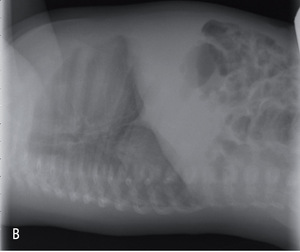

Rycina 3. Zdjęcia przeglądowe tylno-przednie (A) i boczne (B) trzymiesięcznego chłopca z sekwestracją wewnątrzpłatową dolnego płata prawego.